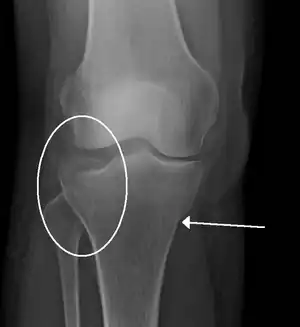

Lipohemarthrosis (presence of fat and blood from bone marrow in the joint space after an intraarticular fracture) seen on X-ray in a person with a subtle tibial plateau fracture -

Subtle tibial plateau fracture on an AP X ray of the knee -